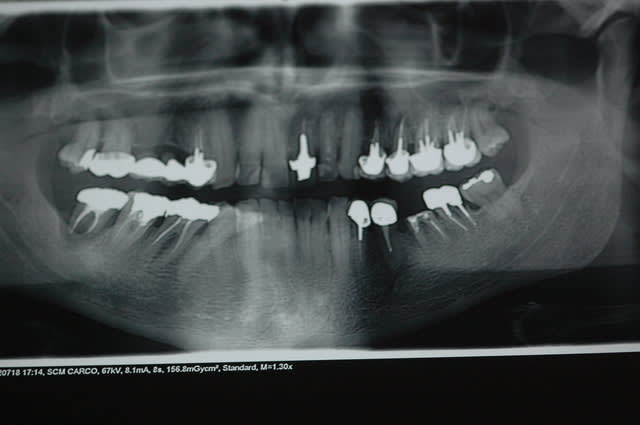

11 et 21 restaurées en 1976 (40ans) 11 sans tenon

la céramique 21 est détruite, tu gardes le tenon tel quel ou pas?

La demande est esthétique les couleurs ont évolué de façon variable avec le temps.